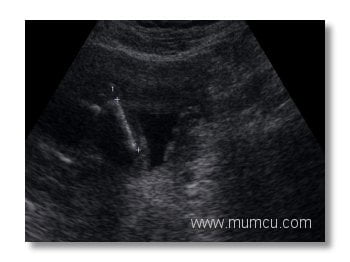

8 haftalık gebelikte amniyon kesesi, yolk kesesi ve embryo

Vajinal ultrasonografi